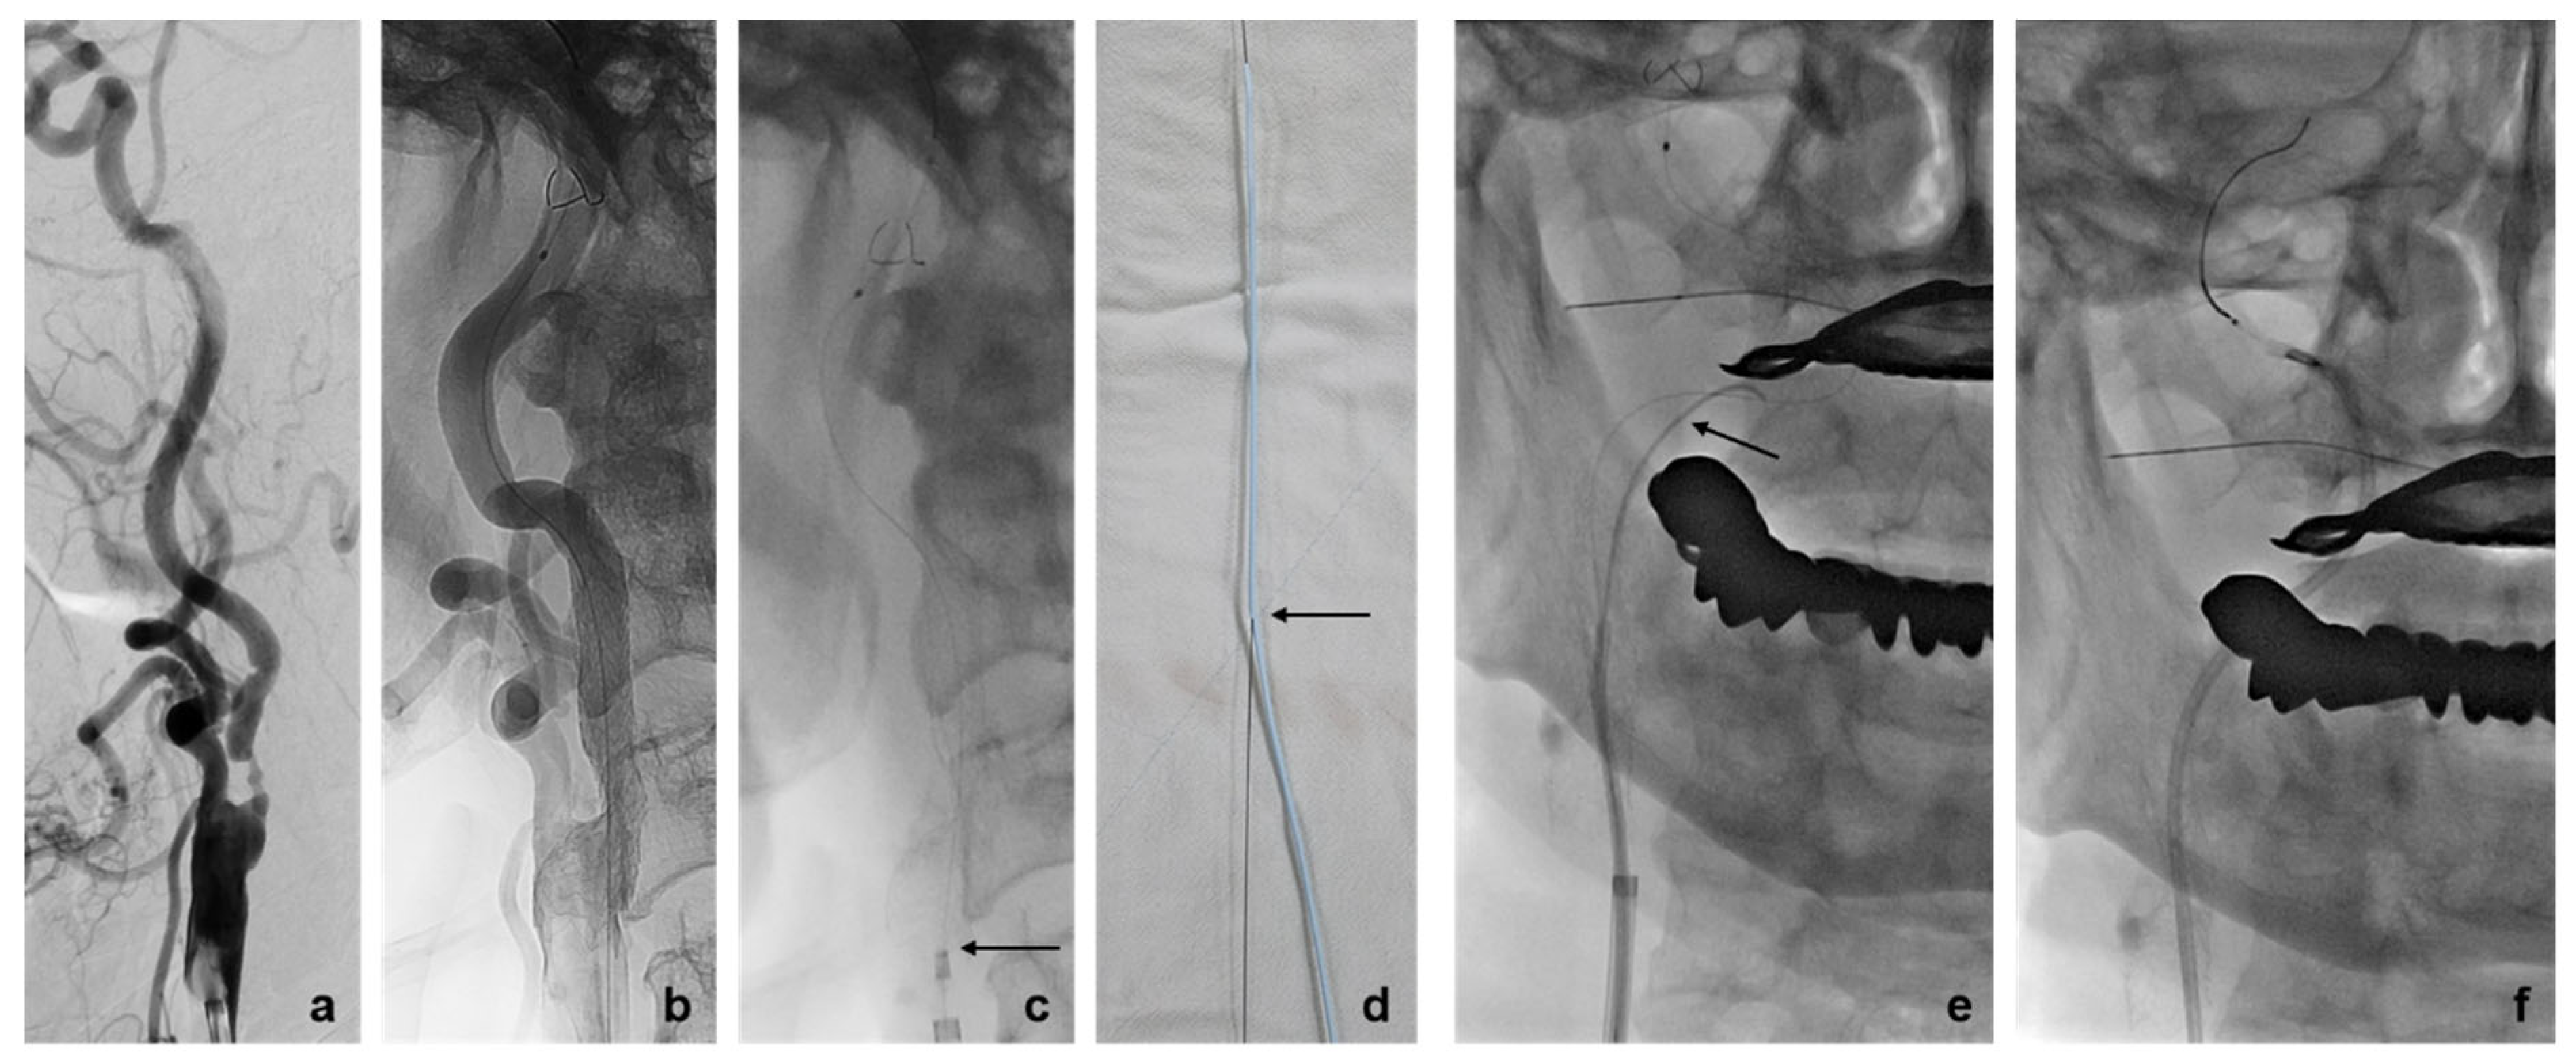

3.2. Rescue Techniques for Adverse Events Related to EPD